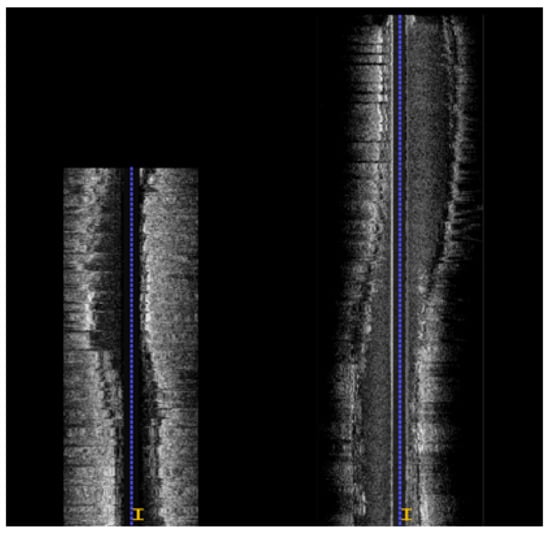

2.2. IVUS Pullbacks Registration

3.2. Longitudinal Registration